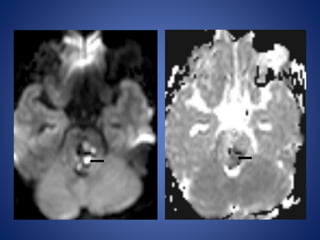

13 yrs male, with history of seizures with cilinical suspicion of febrile

encephalitis.

DWI

ADC

13 yrs male,with history of seizures with cilinical suspicion of febrile encephalitis.